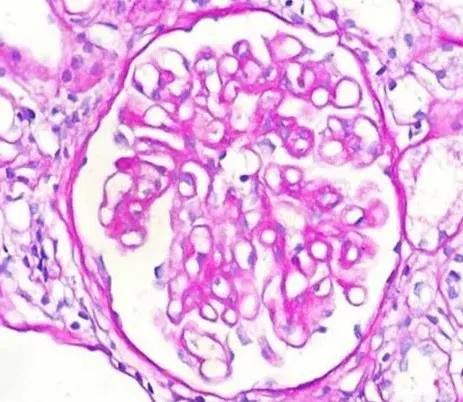

Nefropatía Membranosa: ¿Y si el paciente no responde al tratamiento inicial?

Nefropatía Membranosa: ¿Y si el paciente no responde al tratamiento inicial?

En este video, abordamos estrategias para tratar a pacientes con nefropatía membranosa que no responden al tratamiento inicial. Se enfatiza la importancia de la reevaluación constante y del ajuste del régimen de tratamiento en función de los resultados y del estado del paciente.

Cómo tratar la Nefropatía Membranosa de manera práctica

Cómo tratar la Nefropatía Membranosa de manera práctica